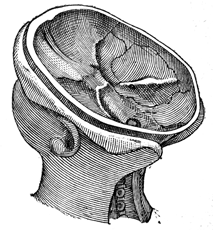

Chapter II—Structure of the Brain.

Man a triple being—Materialists and illusionists misconceive him—Relation

of the soul to the brain and body—The nervous system;

illustration—Embryonic condition—Anatomical descriptions unsatisfactory

and the phrenological school incorrect—Exterior view

of the brain in the head, illustrated and described—The cerebrum,

cerebellum, and tentorium—Interior view of the base of the skull—Bones

of the head illustrated—Division of the brain into lobes

and convolutions, with illustration—Frontal, middle, parietal,

tempero-sphenoidal, and occipital—Anatomical plan or grouping of

convolutions differs from their actual appearance—View of the superior

surface illustrated—Difference between the irregular convolutions

and the angular maps—View of the inferior surface of the

brain—Illustration and description of the parts—Interior view of

section on the median line—Divided and undivided surfaces-Corpus

callosum explained—The two brains and their diagonal

relations to the body—Penetrating and describing the lateral

ventricles—The serum in the brain—Variations of serum and

blood—Variations in hydrocephalus and insanity—Our power to

modify the brain and change our destiny—Power of education—Responsibility

of society—The lateral ventricles the centre of the

brain—Base of the ventricles, the great inferior ganglia of the

brain, corpora striata, and thalami—Their radiating fibres inclosing

a cavity—The thalami and their commissure and third ventricle—The

medulla oblongata, cerebellum, and arbor vitæ—The pons

Varolii and crura of the brain—the corpora quadrigemina, pineal

gland, fourth ventricle, and calamus scriptorius.